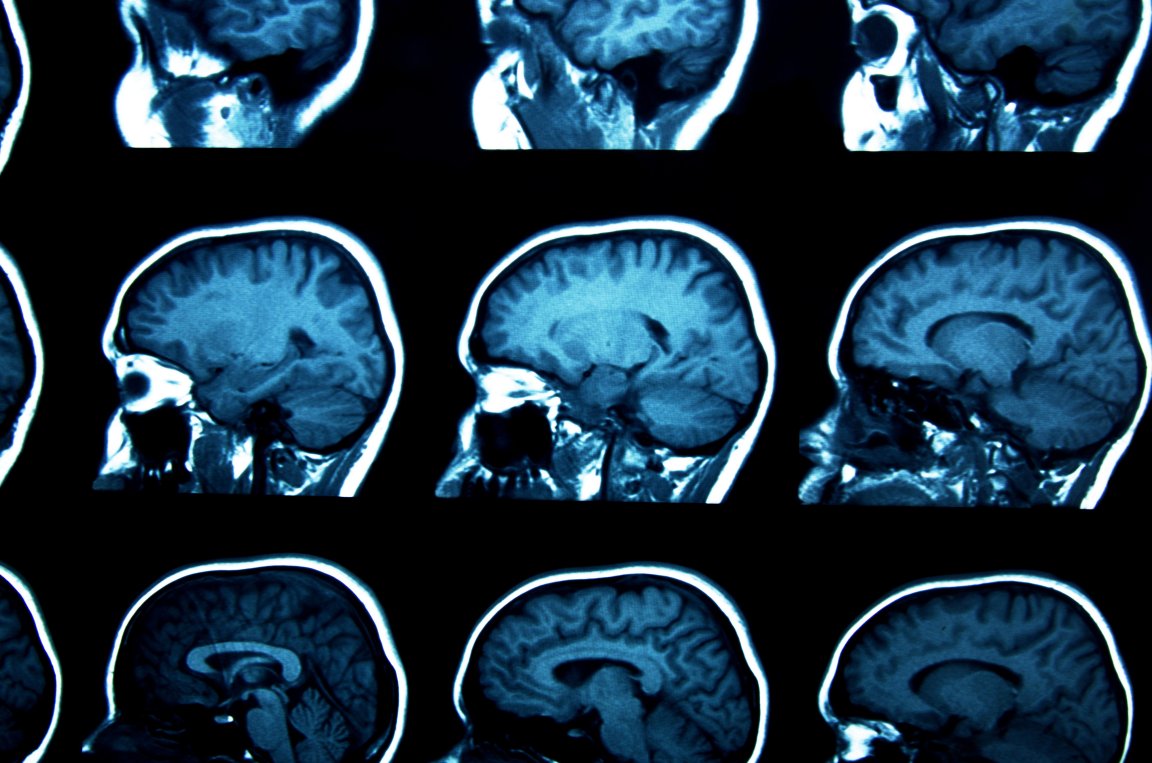

While often misrepresented in the media, schizophrenia is a disease that can have a major impact on the lives of those living with it. Around the world, 21 million people are currently living with the mental illness, the symptoms of which can include paranoia, auditory and visual hallucinations. These symptoms can be severe and debilitating, and can impact every aspect of a person’s life. According to the World Health Organization (WHO), schizophrenia is defined by “profound disruptions in thinking, affecting language, perception, and the sense of self.”

An international team of researchers has found that these life-altering symptoms could be caused by defects in glial cells, the cells that support and insulate nerve cells. By using mice with brains colonized by human-donated glial cells, the team’s discovery could greatly impact the future diagnosis and treatment of schizophrenia.